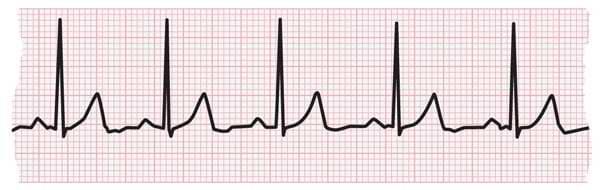

3.1.1.Electrocardiogram (ECG/EKG)

Anon-invasivetestthatrecordstheelectricalactivityofthe heartovertime.Itisusedtodetectarrhythmias,ischemia,

and other heart abnormalities by analyzing the heart's rhythmandelectricalpatterns.

Figure-2: ECG Report